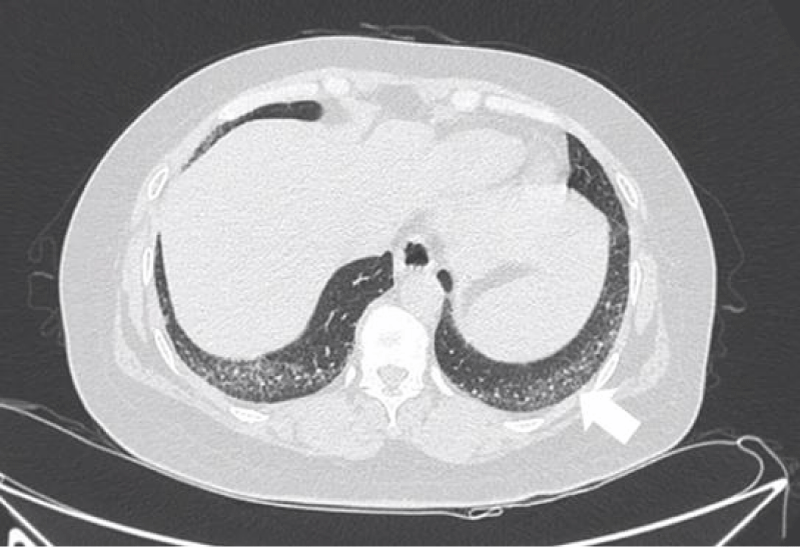

Figure 8: Different levels HRCT images from a 54 year-old male considered as UIP pattern.

The most common pattern in SSc-ILD was NSIP, accounted for 71.6% (83 patients); secondly was UIP, accounted for 25.9%, and 3 patients presented consistent with LIP.

The pathological feature of usual interstitial ipneumonia(UIP) was heterogeneous appearance, showing an alternate distribution of interstitial inflammation, fibrosis and normal lung tissues and can see limits scar formation with dense fibrosis, lead to the destruction and cystic formation of the pulmonary parenchyma similar to honeycomb. On HRCT imaging, UIP appeared as reticular opacities and honeycombing mainly distributed around the lung and under the pleura, with or without traction bronchiectasis [20].